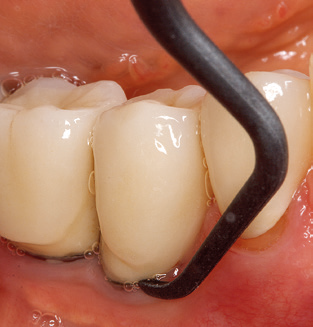

Fig. 4: Flexible probes with millimetre markings are recommended for the probing of dental implants (e.g. Colorvue Kit PCV11KIT6, Hu­Friedy). – Fig. 5a and b: A straight working tip (1P, W&H Dentalwerk Bürmoos GmbH) is a suitable instrument for use on all natural teeth. – Fig. 6: Curved working tips (3Pr/3Pl, W&H Dentalwerk Bürmoos GmbH) lend themselves to the processing of difficult-to-reach areas of the tooth and root surfaces (e.g. furcations). – Fig. 7: The tapered, hexagonal implant cleaning tip (1I, W&H Dentalwerk Bürmoos GmbH) permits atraumatic and efficient cleaning of the crown and abutment surfaces. – Fig. 8: Titanium and carbon curettes are suitable instruments for the manual cleaning of the implant surfaces.

Good illumination of the working field facilitates the process considerably. The system used by the authors achieves this thanks to a 5x LED ring integrated in the handpiece. Naturally, a range of working tips for different indications is also offered. A straight, universally employable tip is the basic instrument required for machine cleaning of natural teeth (Fig. 5a and b). Curved tips, which allow access to exposed furcations, are also available for hard-to-reach areas in the posterior region (Fig. 6).